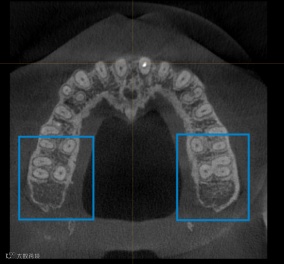

推磨牙的前提是磨牙后方有足够的空间可以让牙齿移动,有的人后方骨量充足可以直接推,有些人可能位置不够,但也可以通过拔除智牙来获得空间。因此,矫正之前需要拍ct详细的检查,才能确认是否适合选择推磨牙的正畸方式。